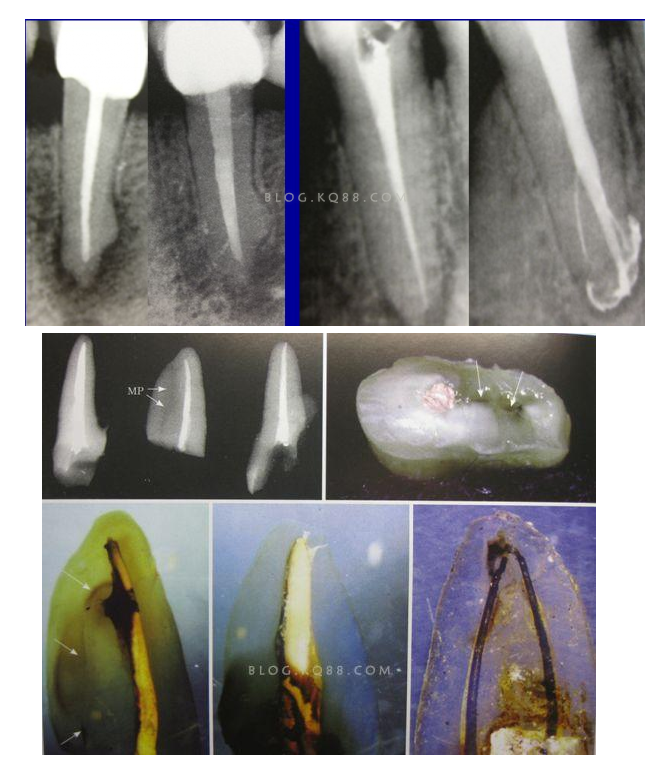

2相信有更多的根管存在 相信根管的數(shù)目比我們想象的多,根管系統(tǒng)的復(fù)雜程度比我們想象的見到的要更復(fù)雜,我們只有用盡所有努力和辦法才可能達(dá)到預(yù)期目標(biāo),對于上 牙合 6的MB2來說過去是偶爾有,現(xiàn)在是偶爾沒有,各種文獻(xiàn)報道的比例也不一致,我在培訓(xùn)班醫(yī)生帶來的離體牙中幾乎沒有見到?jīng)]有的,臨床中也是一樣。對于尋找的方法來說,我覺得相信有才是最重要的,首先相信一定有就會想各種辦法,找到的幾率就會更多。如果有條件在顯微鏡和超聲的配合下效率會更高。

3、感染控制決定成敗 根管治療中感染控制的徹底程度直接決定根管治療的成功率,對主根管、牙本質(zhì)小管、側(cè)支根管的控制同等重要;完善根管治療后的患牙失敗主要原因是根管系統(tǒng)的頑固的感染或根尖周頑固的根管外細(xì)菌感染,當(dāng)然也有可能是非細(xì)菌性因素,但根管內(nèi)的感染占主要原因。在高效率的機(jī)械預(yù)備根管時,一定要用專用的側(cè)方開口針頭的注射器大量多次的沖洗根管,次氯酸鈉要加熱后使用,并及時補(bǔ)充新鮮的液體到根管系統(tǒng),EDTA液體的使用可以很好去除根管預(yù)備中產(chǎn)生的玷污層,1%的CHX液體可以在30秒內(nèi)殺滅糞腸球菌,并且有延緩作用,是優(yōu)秀的終末沖洗液。超聲蕩洗清理根管的效果要優(yōu)于手工沖洗。很多醫(yī)生考慮次氯酸鈉的濃度,其實次氯酸鈉沖洗液的濃度并不重要,重要的是沖洗的時間和次數(shù),更換新鮮液體的頻率和液體是否加熱。

4、敢于否定自己 有些病例看上去似乎是完美的,但是患者就是感覺有明顯的不適感,就應(yīng)該考慮是否有未處理的根管內(nèi)感染區(qū)域,分析是根管、峽部、分支、縫隙等原因后就要及時的采取措施,失敗病例的處理方法選擇非手術(shù)再治療還是手術(shù)再治療,一般首選非手術(shù)再治療,但要評估再治療的預(yù)期結(jié)果,如果非手術(shù)再治療的對患牙的創(chuàng)傷太大或預(yù)期效果不確定就考慮手術(shù)再治療,全面考慮分析后決定方法。要及時的決定下一步的處理方法。長期的反復(fù)的復(fù)診觀察是沒有意義的,最后的結(jié)果是流失患者。